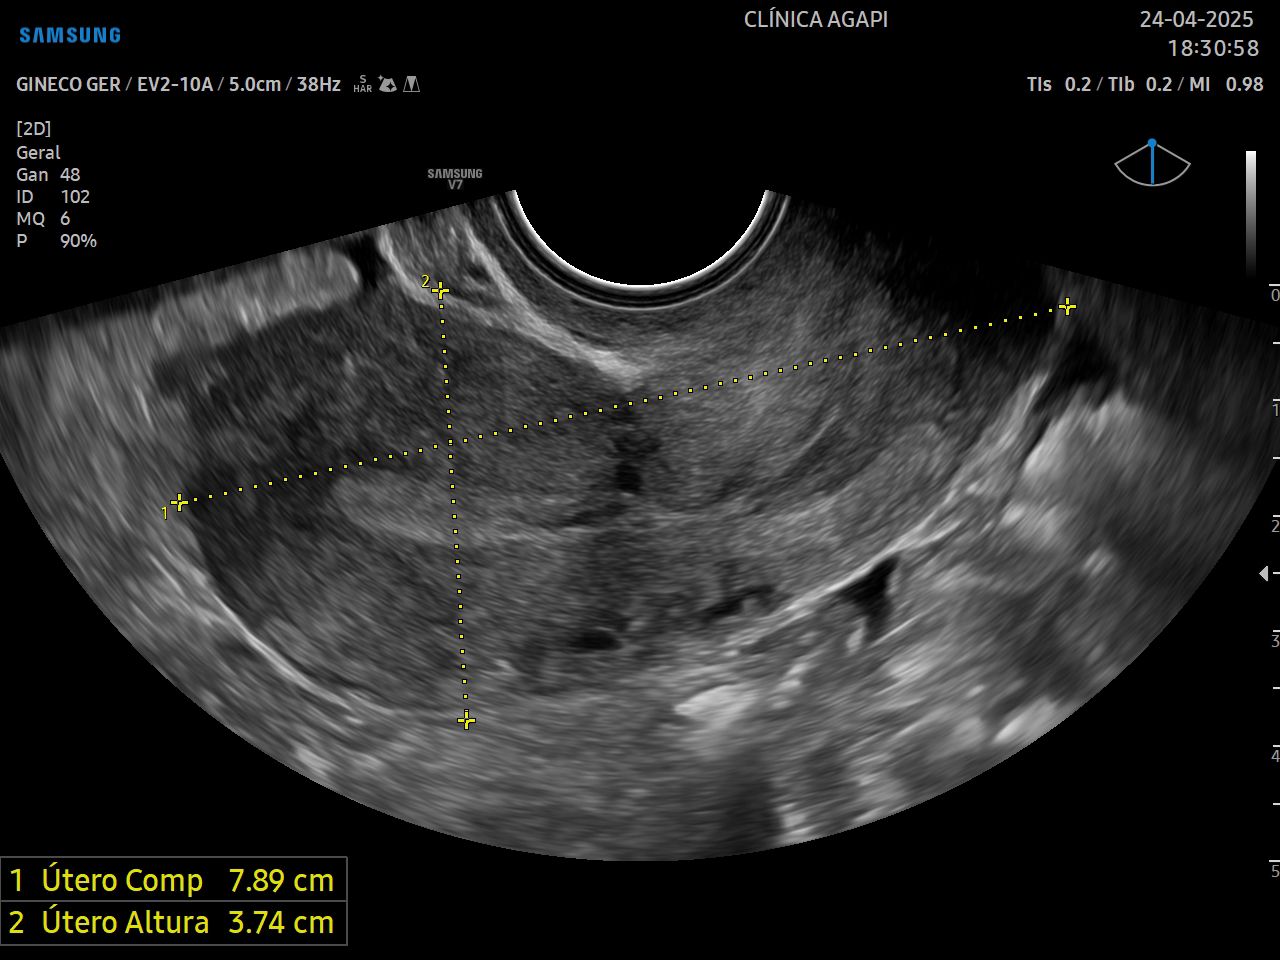

Avalia o útero e os ovários, assim como a presença de outras estruturas como massas, cistos e tumores pélvicos. Indicado para mulheres que já iniciaram a vida sexual, sendo realizado via transvaginal.

Pode ser realizado de rotina ou para avaliação de sintomas específicos.

O exame não exige um preparo específico, apenas que a paciente remova absorventes internos ou coletores menstruais antes do exame, se for o caso. Pode ser realizado mesmo com menstruação ou sangramento irregular.